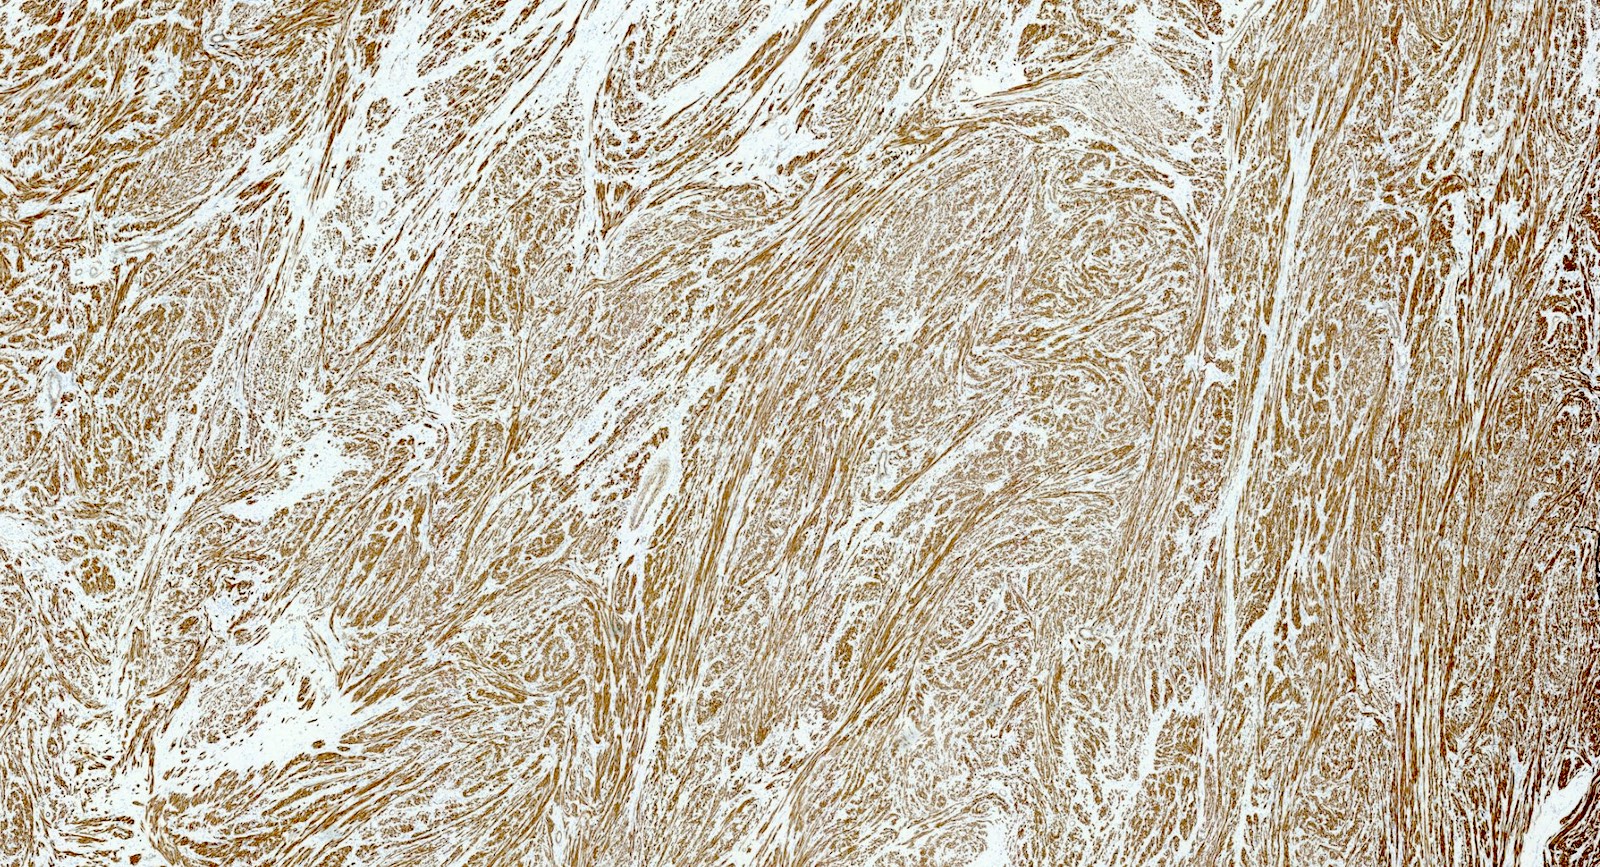

Positive stains

- Desmin

- h-caldesmon

- Smooth muscle actin

- Transgelin

- Smooth muscle markers can be weak in epithelioid and myxoid leiomyomas

- Estrogen and progesterone receptors

- WT1

- Up to 40% of leiomyomas are CD10 positive (especially cellular leiomyomas) (Am J Surg Pathol 2002;26:403)

Microscopic (histologic) images

Contributed by Sabrina Croce, M.D., Ph.D., Kristina Doytcheva, M.D., Jennifer A. Bennett, M.D. (Case #508) and @Andrew_Fltv on Twitter

- Comment: Microscopic examination reveals a smooth muscle tumor composed of spindle, cigar shaped cells arranged in fascicular pattern without cytologic atypia and tumor cell necrosis. Mitoses are rare (4 mitoses/10 high power fields). Tumor borders are well circumscribed. By immunohistochemistry the tumor cells are positive for desmin, h-caldesmon, ER and PR.